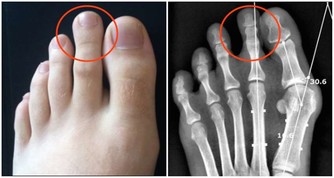

世界上沒有不衰老的血管,正常人的血管每年變窄1%-2%;有高血壓、高血黏度、糖尿病者,每年變窄3%-4%或以上。

當動脈血管堵塞75%以上,血流量過少時,胸悶、氣短、頭暈、頭痛等不適就會出現,更嚴重還會誘發腦卒中、心肌梗死等疾病。